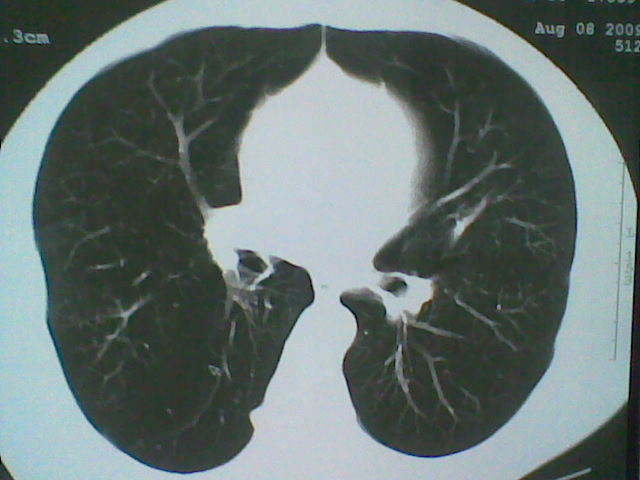

标题: CT21512:支扩伴感染?

患者女。咳嗽数天,咯血半天。

我们报的是支扩伴感染?

支扩伴感染。

支持楼主意见,考虑支气管扩张并感染。

支气管扩张并感染。